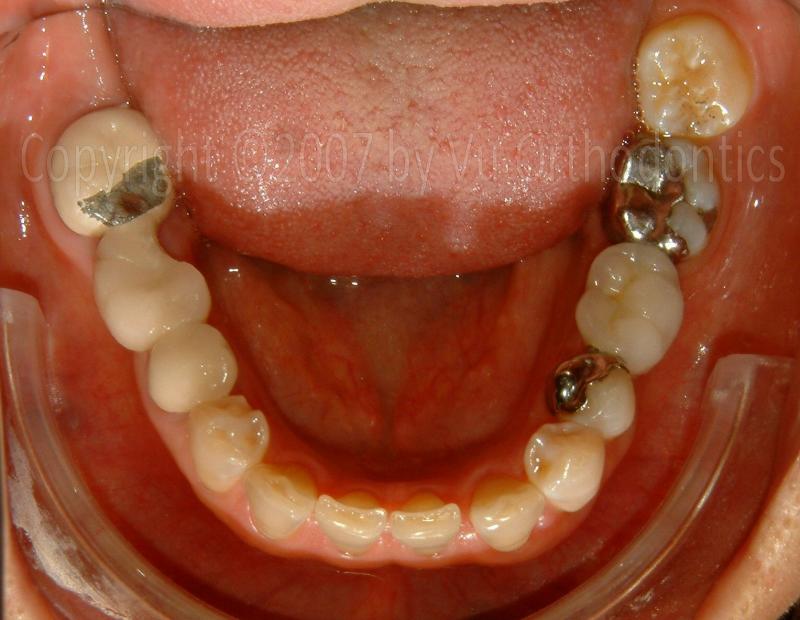

A Case that needs Free Gingival Graft (FGG)

For many patients, the posterior of the lower arch needs Free Gingival Graft (FGG) because of poor quality of keratinized mucosa. The case, infra, shows as an example.

Fig. 9. A broken 3-unit bridge (for the missing Tooth #30)

Fig. 10. Poor keratinized mucosa on the buccal side of the implant (with healing abutment)

Fig. 11. After the implant was buried (w/ a cap screw), ready for Free Gingival Graft (FGG), poor keratinized mucosa was apparent

Fig. 12. FGG was performed

Fig. 13. The donor site on the palate, for the FGG

Fig. 14. At the end, good keratinized mucosa is apparent (good seal/protection for the implant, after FGG)